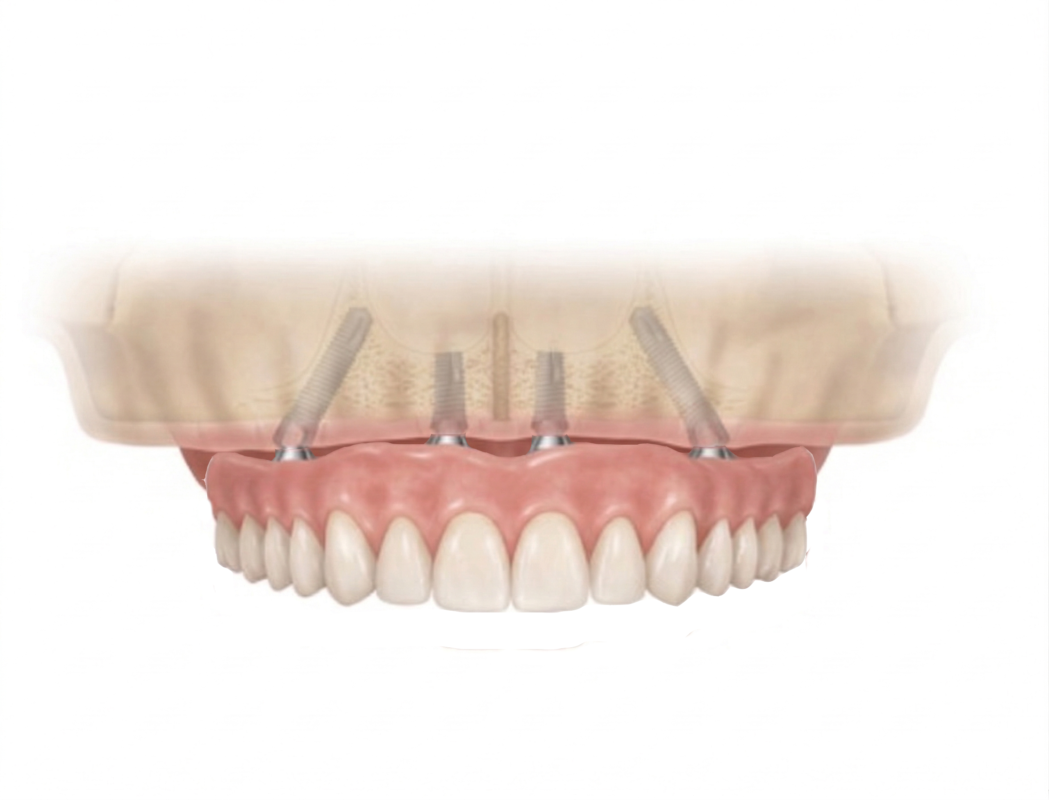

The first step is installing tooth implants is embedded the implant posts into the jaw bone. In this illustration, 4 implants are placed into the jaw bone. After implant placements, your dentist makes a re-check appointment about 5 to 7 days later to re-check the implant wound healing.

2. INSTALLING THE TOOTH IMPLANTS